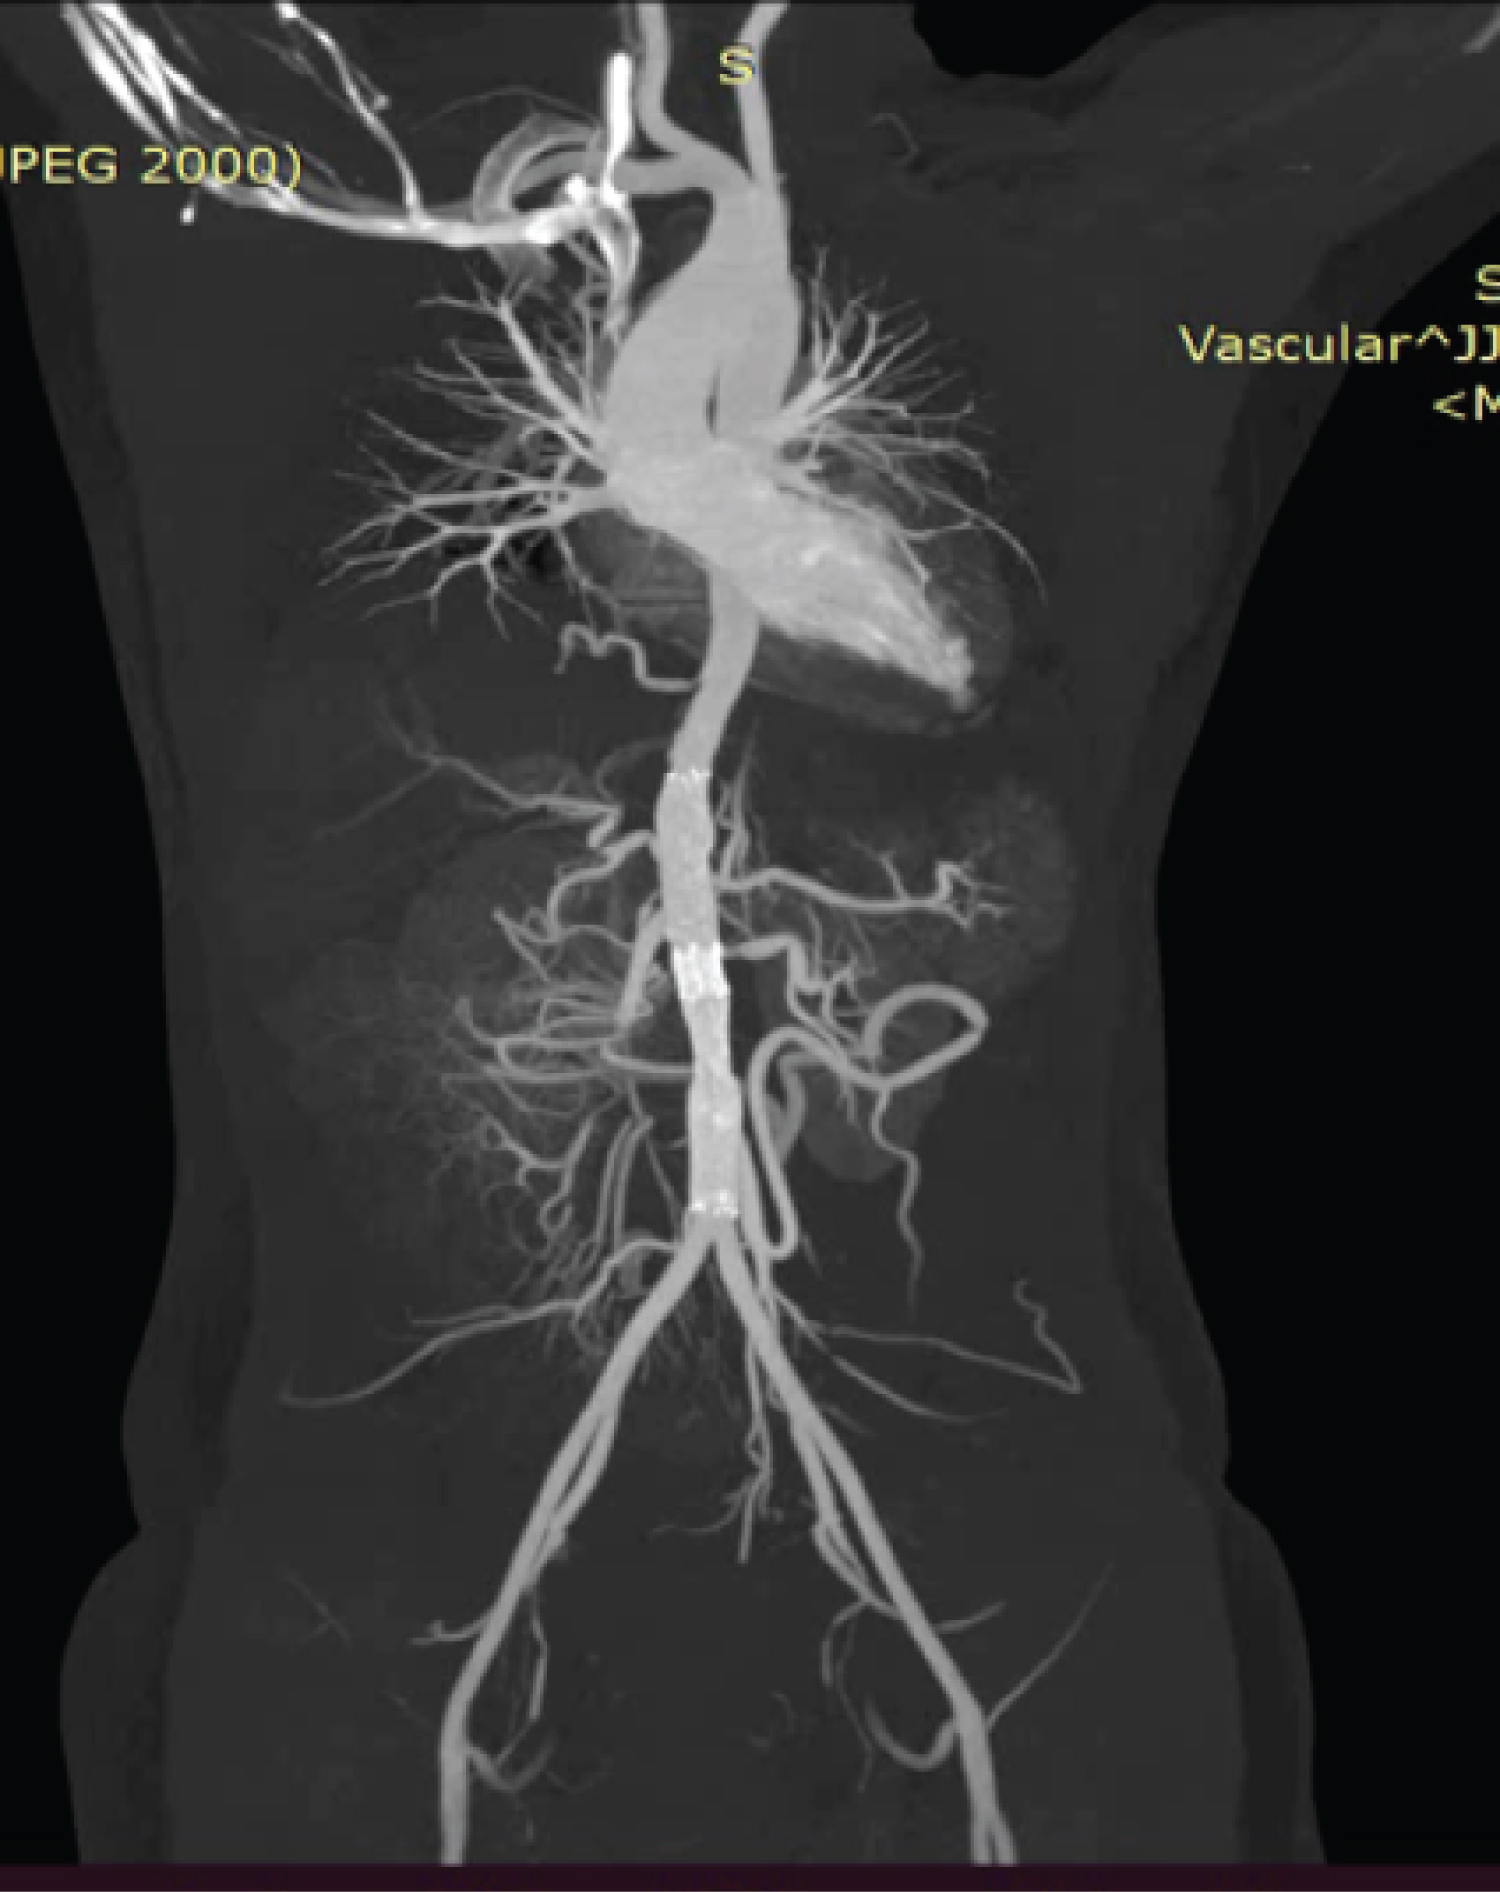

The procedure, performed under local anesthesia, involved a right femoral artery puncture. Heparin (100 IU/kg) was administered intravenously. A headhunter catheter was passed through the right femoral artery, revealing a distal flap in the infrarenal part, causing confusion regarding true or false lumen (Figure 2). To clarify, a left brachial artery access was taken, confirming the true lumen. The catheter was advanced, confirming total cutoff in the infra-renal aorta (Figure 3). Further, a terumo 0.035 wire was passed through the catheter and snared out through the right femoral artery access, and a multi-marker pigtail catheter was passed over it. A check shoot by pigtail shows similar findings as the CT aortogram. The lesion in the aorta was sequentially balloon-dilated with Cordis POWERFLEX PRO 12 mm × 6 cm balloon. Post-balloon dilatation check shoot shows improved distal flow. The suprarenal segment was stented with the Cordis SMART CONTROL NITINOL stent 14 mm × 60 mm, and the infrarenal segment was stented with the SMART CONTROL STENT 12 mm × 80 mm, with around 10 mm overlapping with the first stent (Figure 4-left image). The post-stent angiogram reveals good flow across the aorta with improved distal circulation with slow flow in right renal artery which we thought would improve by anticoagulation (Figure 4-right image). Five days after aortic angioplasty, the patient complained of persistent abdominal pain, and hypertension persisted. So, we decided to conduct a repeat CT Aortogram. The repeat CT Aortogram revealed a patent stent with good flow, and the celiac, SMA, IMA, bilateral common, external, and internal iliac were normal. There was a critical stenosis (> 80% ostial stenosis) in the left renal artery and right renal artery total cut off from ostium (Figure 5). Consequently, we proceeded with PTRA. A check shoot with a sim catheter showed similar finding as of CT Aortogram. A 0.014 wire was crossed, and the right renal artery ostium was dilated using a 4.5 × 20 mm PIPIT balloon. The right renal artery was stented with a RENOFIT 5 × 15 mm stent. The left renal artery was stented with a RENOFIT 6 × 15 mm stent. Post-angioplasty revealed bilateral good-caliber renal arteries with good flow (Figure 6). Thirty minutes after the procedure, the patient developed right hemiparesis. On examination, the patient was conscious, oriented, with power of 2/5 in both upper limbs and lower limbs. NCCT showed left ganglio-capsular intraparenchymal bleed, which was managed conservatively. Post-renal stenting, the patient's abdominal pain diminished and blood pressure significantly came down. After 10 days, the patient was discharged with power of 4/5 in both upper and lower limbs in an ambulatory condition. Hypertension was well controlled with only amlodipine 5 mg. The patient has been doing well for the last 11 months with a single antiplatelet agent.

Figure 4: Left side- Suprarenal segment was stented with the Cordis SMART CONTROL NITINOL stent 14 mm × 60 mm, and the infrarenal segment were stented with the SMART CONTROL STENT 12 mm × 80 mm, with around 10 mm overlapping with the first stent; Right side image- Post-stenting angiogram reveals good flow across the aorta with improved distal circulation. View Figure 4

Figure 5: Repeat CT Aortogram revealed a patent stent with good flow, and the celiac, SMA, IMA, bilateral common, external, and internal iliac were normal. There was a critical stenosis (> 80% ostial stenosis) in the left renal artery and right renal artery total cut off from ostium. View Figure 5